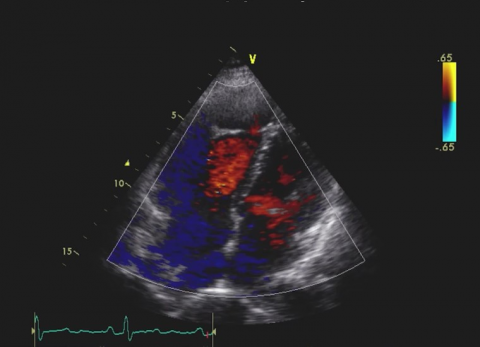

Rozdział 5

Zastawka trójdzielna

Przypadki dla początkujacych